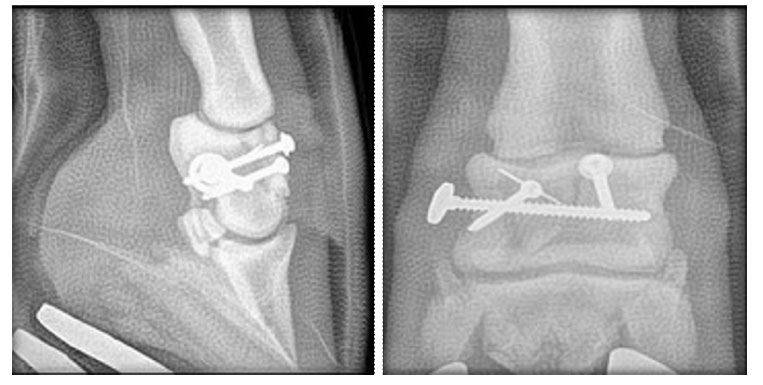

Se expone aspecto dorso-proximal de la segunda falange donde se suturan fragmentos múltiples con material vicril 2-0 con patrón simple interrumpido. Posteriormente se realiza reducción de la fractura y se aplica tornillos corticales de 3.5 y 2.7 correspondientes al fragmento dorso-proximal. Luego se realiza reducción de la fractura palmar mediante la aplicación de tornillo cortical de 4.5 (Figura 3), procedimientos que se realizan mediante guía radiológica digital (Figura 4). Se sutura el extensor digital común con material vicril 2-0 con patrón simple continuo, y la piel con monofilamento corpalone 2-0 patrón simple continuo. Por último se aplica yeso y la paciente continua con tratamiento antibiótico de amplio espectro y antiinflamatorios.

Figura 3 Reducción de la fractura de la falange media del miembro anterior de una potranca de 4.5 años con tornillos corticales relacionados a los fragmentos dorso-proximal y palmar

Figura 4 Imagen radiológica de la reducción de la fractura la fractura de la falange media del miembro anterior de una potranca de 4.5 años mediante clavos corticales